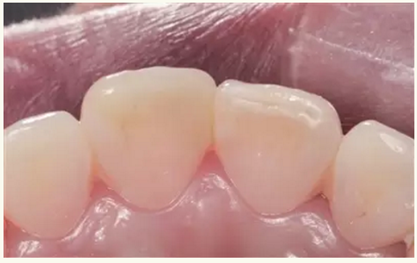

▲術(shù)后即刻(唇側(cè))

▲術(shù)后一月(唇側(cè))